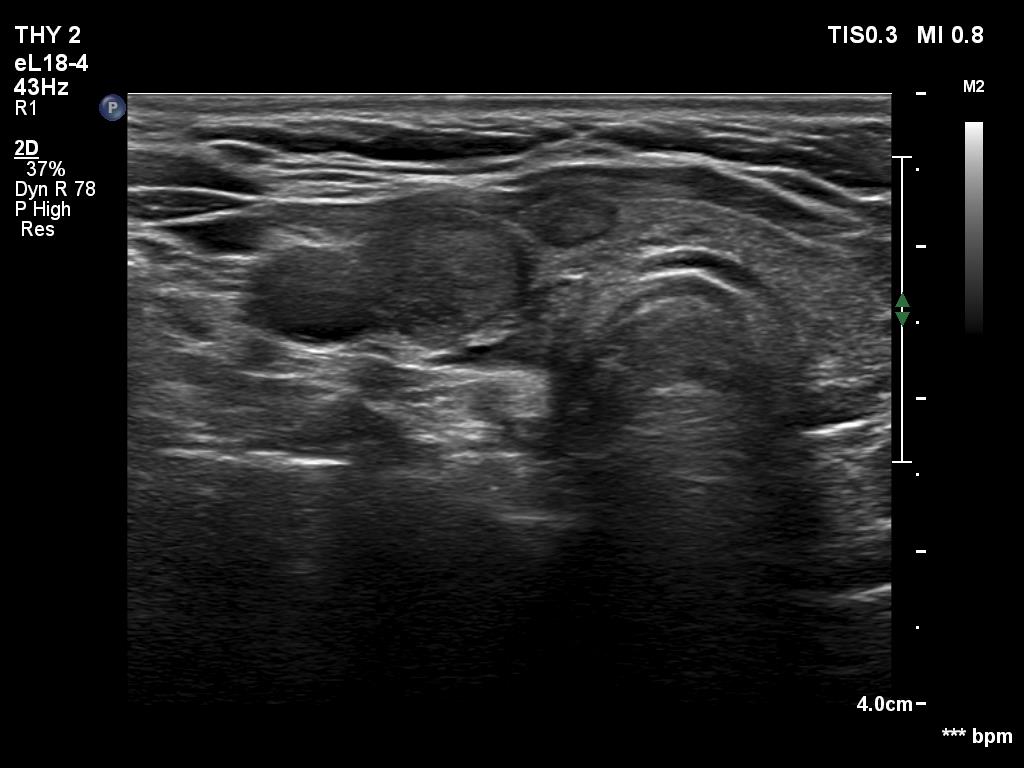

Examination 3 months later (second row of images):

Clinical presentation: The patient had no complaints.

Palpation: no abnormality.

Laboratory tests: TSH 5.87 mIU/L, FT4 8.1 pM/L, CRP 0.2 mg/L.

Ultrasonography: The thyroid has decreased in size. The echogenicity and the vascularity of the right lobe remained unchanged while those of the left lobe became almost normal.

Suggestion. Follow-up in six months.